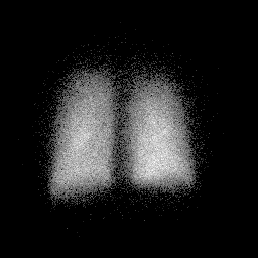

Posterior Perfusion Posterior Ventilation

norm_perf.gif (12668 bytes) norm_vent.gif (11969 bytes)